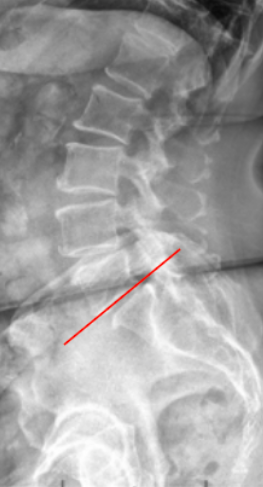

McNab’s Line is a radiographic assessment of the lumbosacral junction alignment, specifically evaluating the angular relationship between the inferior endplate of L5 and the superior surface of S1.

• Obtain a standing lateral lumbar X-ray that includes the lumbosacral junction (L4–S1).

• Draw a tangent line along the inferior endplate of L5.

• Assess for intersection with the superior surface of the sacrum

• Intersection suggests spondylolysis

• Normal segmental alignment: tangent line does not cross superior surface of sacrum; physiologic lumbosacral lordosis

• Hyperlordotic segment: tangent line crosses posterior portion of superior surface of sacrum; often compensatory in anterior shear (spondylolisthesis)

• Hypolordotic/flat segment: tangent line crosses anterior portion of superior surface of sacrum; suggests disc height loss, segmental kyphosis, or early instability